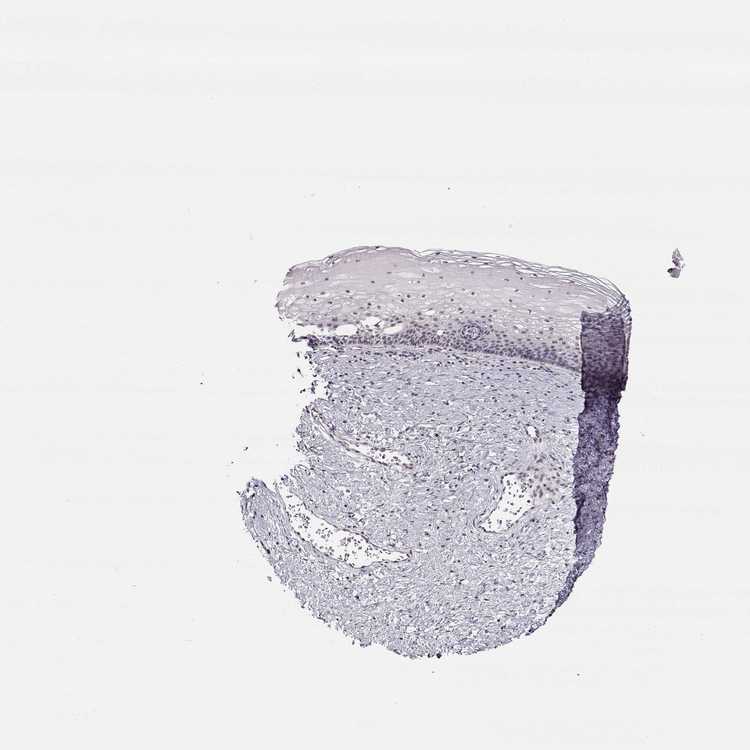

CERVIX - Antibody stainingi

Antibody staining in the annotated cell types in the current human tissue is reported as not detected, low, medium, or high, based on conventional immunohistochemistry profiling in selected tissues. This score is based on the combination of the staining intensity and fraction of stained cells.

Each image is clickable and will lead to virtual microscopy that enables deeper exploration of all samples and also displays staining intensity scores, fraction scores and subcellular localization as well as patient and tissue information for each sample.

Antibody HPA064696

Glandular cells Low

Squamous epithelial cells Not detected

Information about each individual sample is listed below, including gender, age, a tissue section image and estimated fractions of cell types. nTPM (normalized transcripts per million) values give a quantification of the gene abundance which is comparable between different genes and samples.

Female, age 44

Cervix sample 374

nTPM: 13.8

Cell types%

Glandular cells:

10

Squamous epithelial cells:

5

Smooth muscle cells:

65

Other cell types:

20